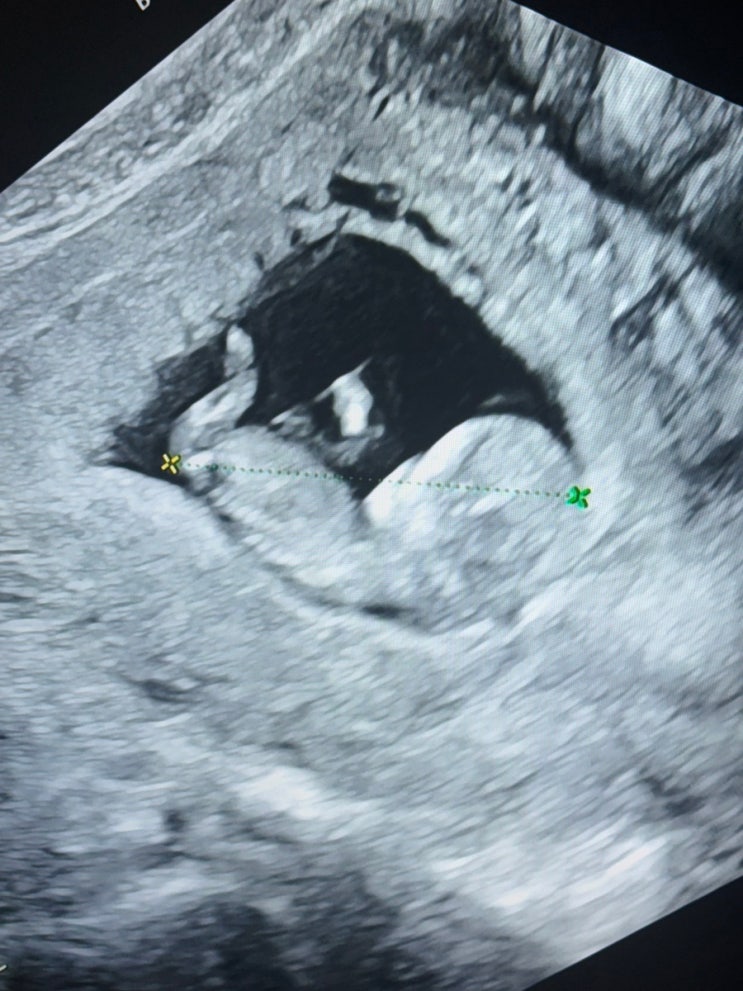

울산 임신 12주 1차 기형아검사 초음파 가격 보람병원 의사추천

울산 임신 12주 1차 기형아검사 병원비 가격 보람병원 의사추천 입니다. 저는 간호사 친구와 이사장님 추천...